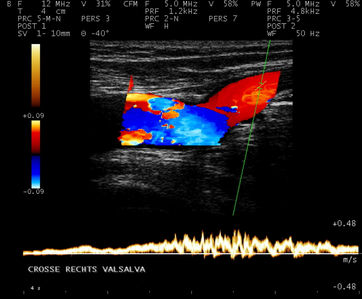

Sowohl die Funktion als auch die Morphologie der Venen können mit der Farbdopplersonographie beurteilt werden.

Normale Funktion der Mündungsklappe an der Einmündung der Vena saphena magna in die Vena femoralis